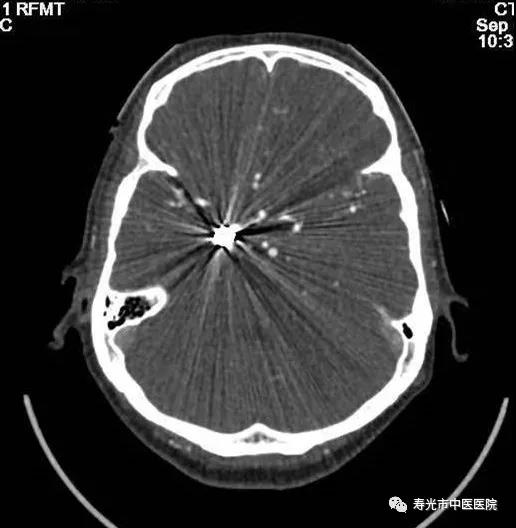

CT检查:清晰成像 挑战重疾

256排Revolution CT被称为“革命型CT”、“CT界的航母”,融合超高端CT的能谱扫描、高时间分辨率扫描和宽体探测器扫描三个领域顶尖科技于一身,实现了无限制1-Beat心脏成像、无限制1-Stop脑卒中成像、多通道主机能谱成像,打造了CT覆盖范围、速度、图像质量、辐射剂量、能谱和扫描舒适性的业界新典范,建立了心血管、神经、肿瘤、呼吸系统、泌尿系统及骨科专业等疾病的成像和低剂量筛查领域全新标准,大幅提高医疗效率和患者体验,有效协助医生进行精准诊断和应对重疾挑战。

去伪影技术更是极大帮助了医生进行治疗。有一位患者,曾经做过脑动脉瘤手术,不久前又出现症状,需要再进行脑血管成像。可是患者脑部已经置入了金属,使用普通CT扫描时,金属会带来反射,排出来的照片一片模糊根本看不清楚病灶。他慕名来到寿光市中医医院求助,在这里,医生利用这台CT的去伪影技术,对他进行了扫描,扫描成像非常清楚。这成了该设备去伪影技术的一个经典病例,美国GE公司的培训师特意将影像搜集去,将在全世界范围进行分享。

CT去伪影扫描效果对比